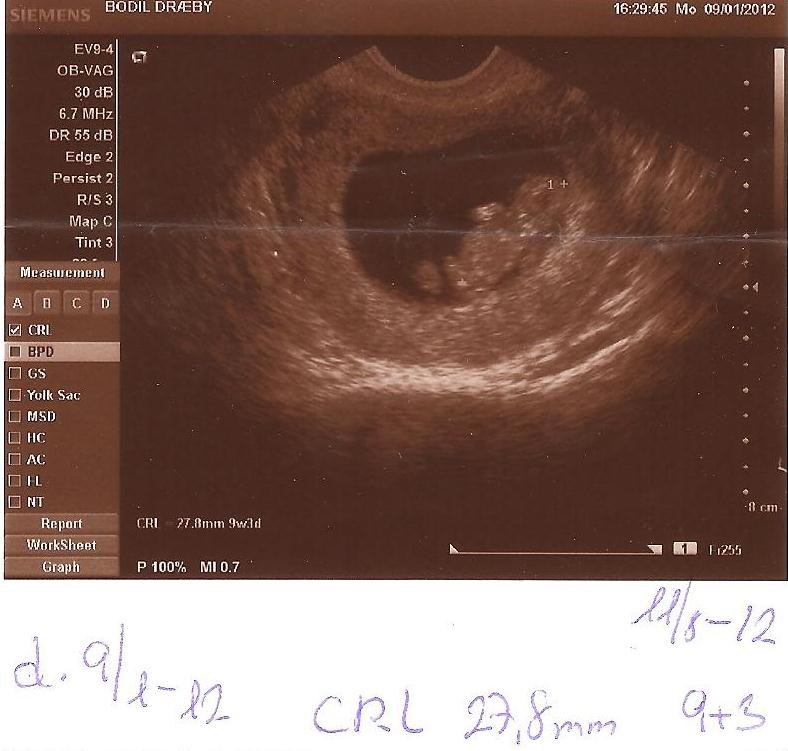

Jeg var til udvendig scanning 7+6, der kunne man se alt hvad man skulle se.

Den læge, der scannede mig, sagde det slet ikke var nødvendigt med indvendig scanning, men han er altså også meget erfaren.